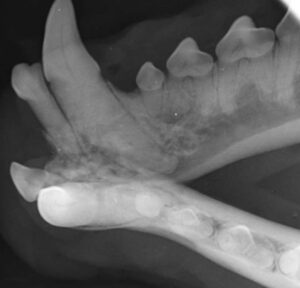

Bonny-Hills-Vet—Dental